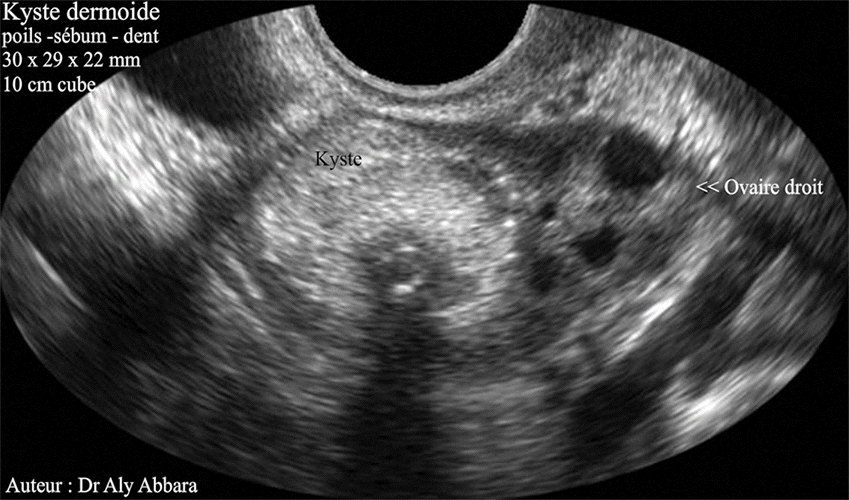

L'aspect échographique et l'aspect macroscopique d'un tératome bénin (kyste dermoïde) de l'ovaire droit mesurant (30 x 29 x 22 mm, soit 10 cm3) contenant outre des poils et du sébum, une dent (incisive parfaitement formée).